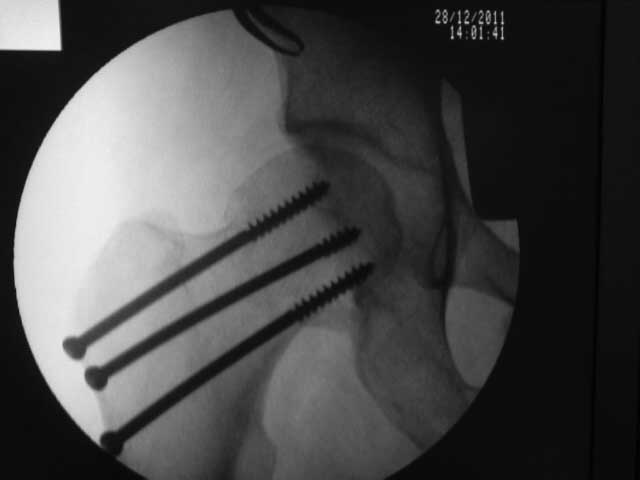

результат, в конце операции.

Винты немного вертикальнее провести и было бы красивее.

>Винты немного вертикальнее провести и было бы красивее

Правильная техника фиксации - это три параллельных каннюлированных винта под углом 130 -135 градусов к диафизу, не ниже уровня малого вертеля. Проведенные ниже вертела винты с бОльшим углом (более вертикальные) в 20% осложнялись подвертельными переломами бедра. Ближе к кортикальному слою винты с длинным контактом резбовой части, а также каннюлирванные механически лучше, чем сплошные. Расположение винтово - в в виде V т.е. один внизу по калькару и два сверху-спереди и сзади.